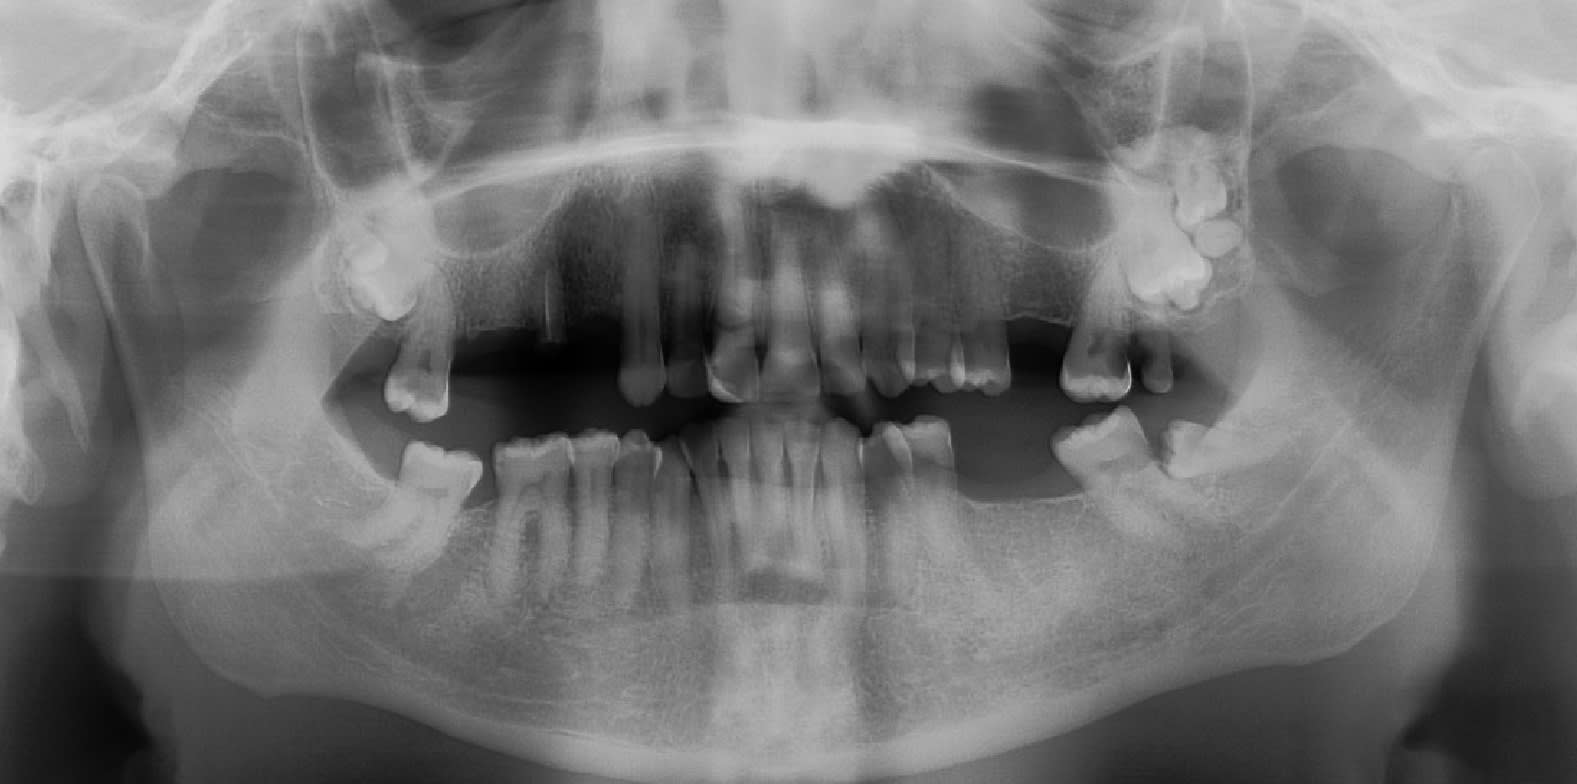

Juste pour partager ce cas avec vous. C'est la première fois que je vois autant de DDS!!

Wisdom-inception...